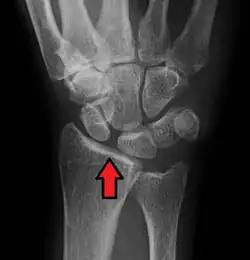

Dynamic scapholunate instability visible upon clenching the wrist -

Scapholunate ligament disruption associated with a Colles' fracture